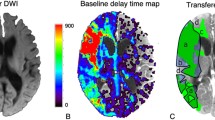

Patients with suspected minor stroke (National Institutes of Health Stroke scale, NIHSS < 4) were screened for the analysis of non-contrast computerized tomography (NCCT) at admission and compared to follow-up MRI. The MRI-based WML volume and visual Fazekas scores were assessed as the gold standard reference. We employed a recently published probabilistic brain segmentation algorithm for CT images to determine the tissue-specific density of WM space. All voxel-wise densities were quantified in WM space and weighted according to partial probabilistic WM content. The resulting mean weighted density of WM space in NCCT, the surrogate of WML, was correlated with reference to MRI-based WML parameters.

The process of CT-based tissue-specific segmentation was reliable in 79 cases with varying severity of microangiopathy. Voxel-wise weighted density within WM spaces showed a noticeable correlation (r = −0.65) with MRI-based WML volume. Particularly in patients with moderate or severe lesion load according to the visual Fazekas score the algorithm provided reliable prediction of MRI-based WML volume.